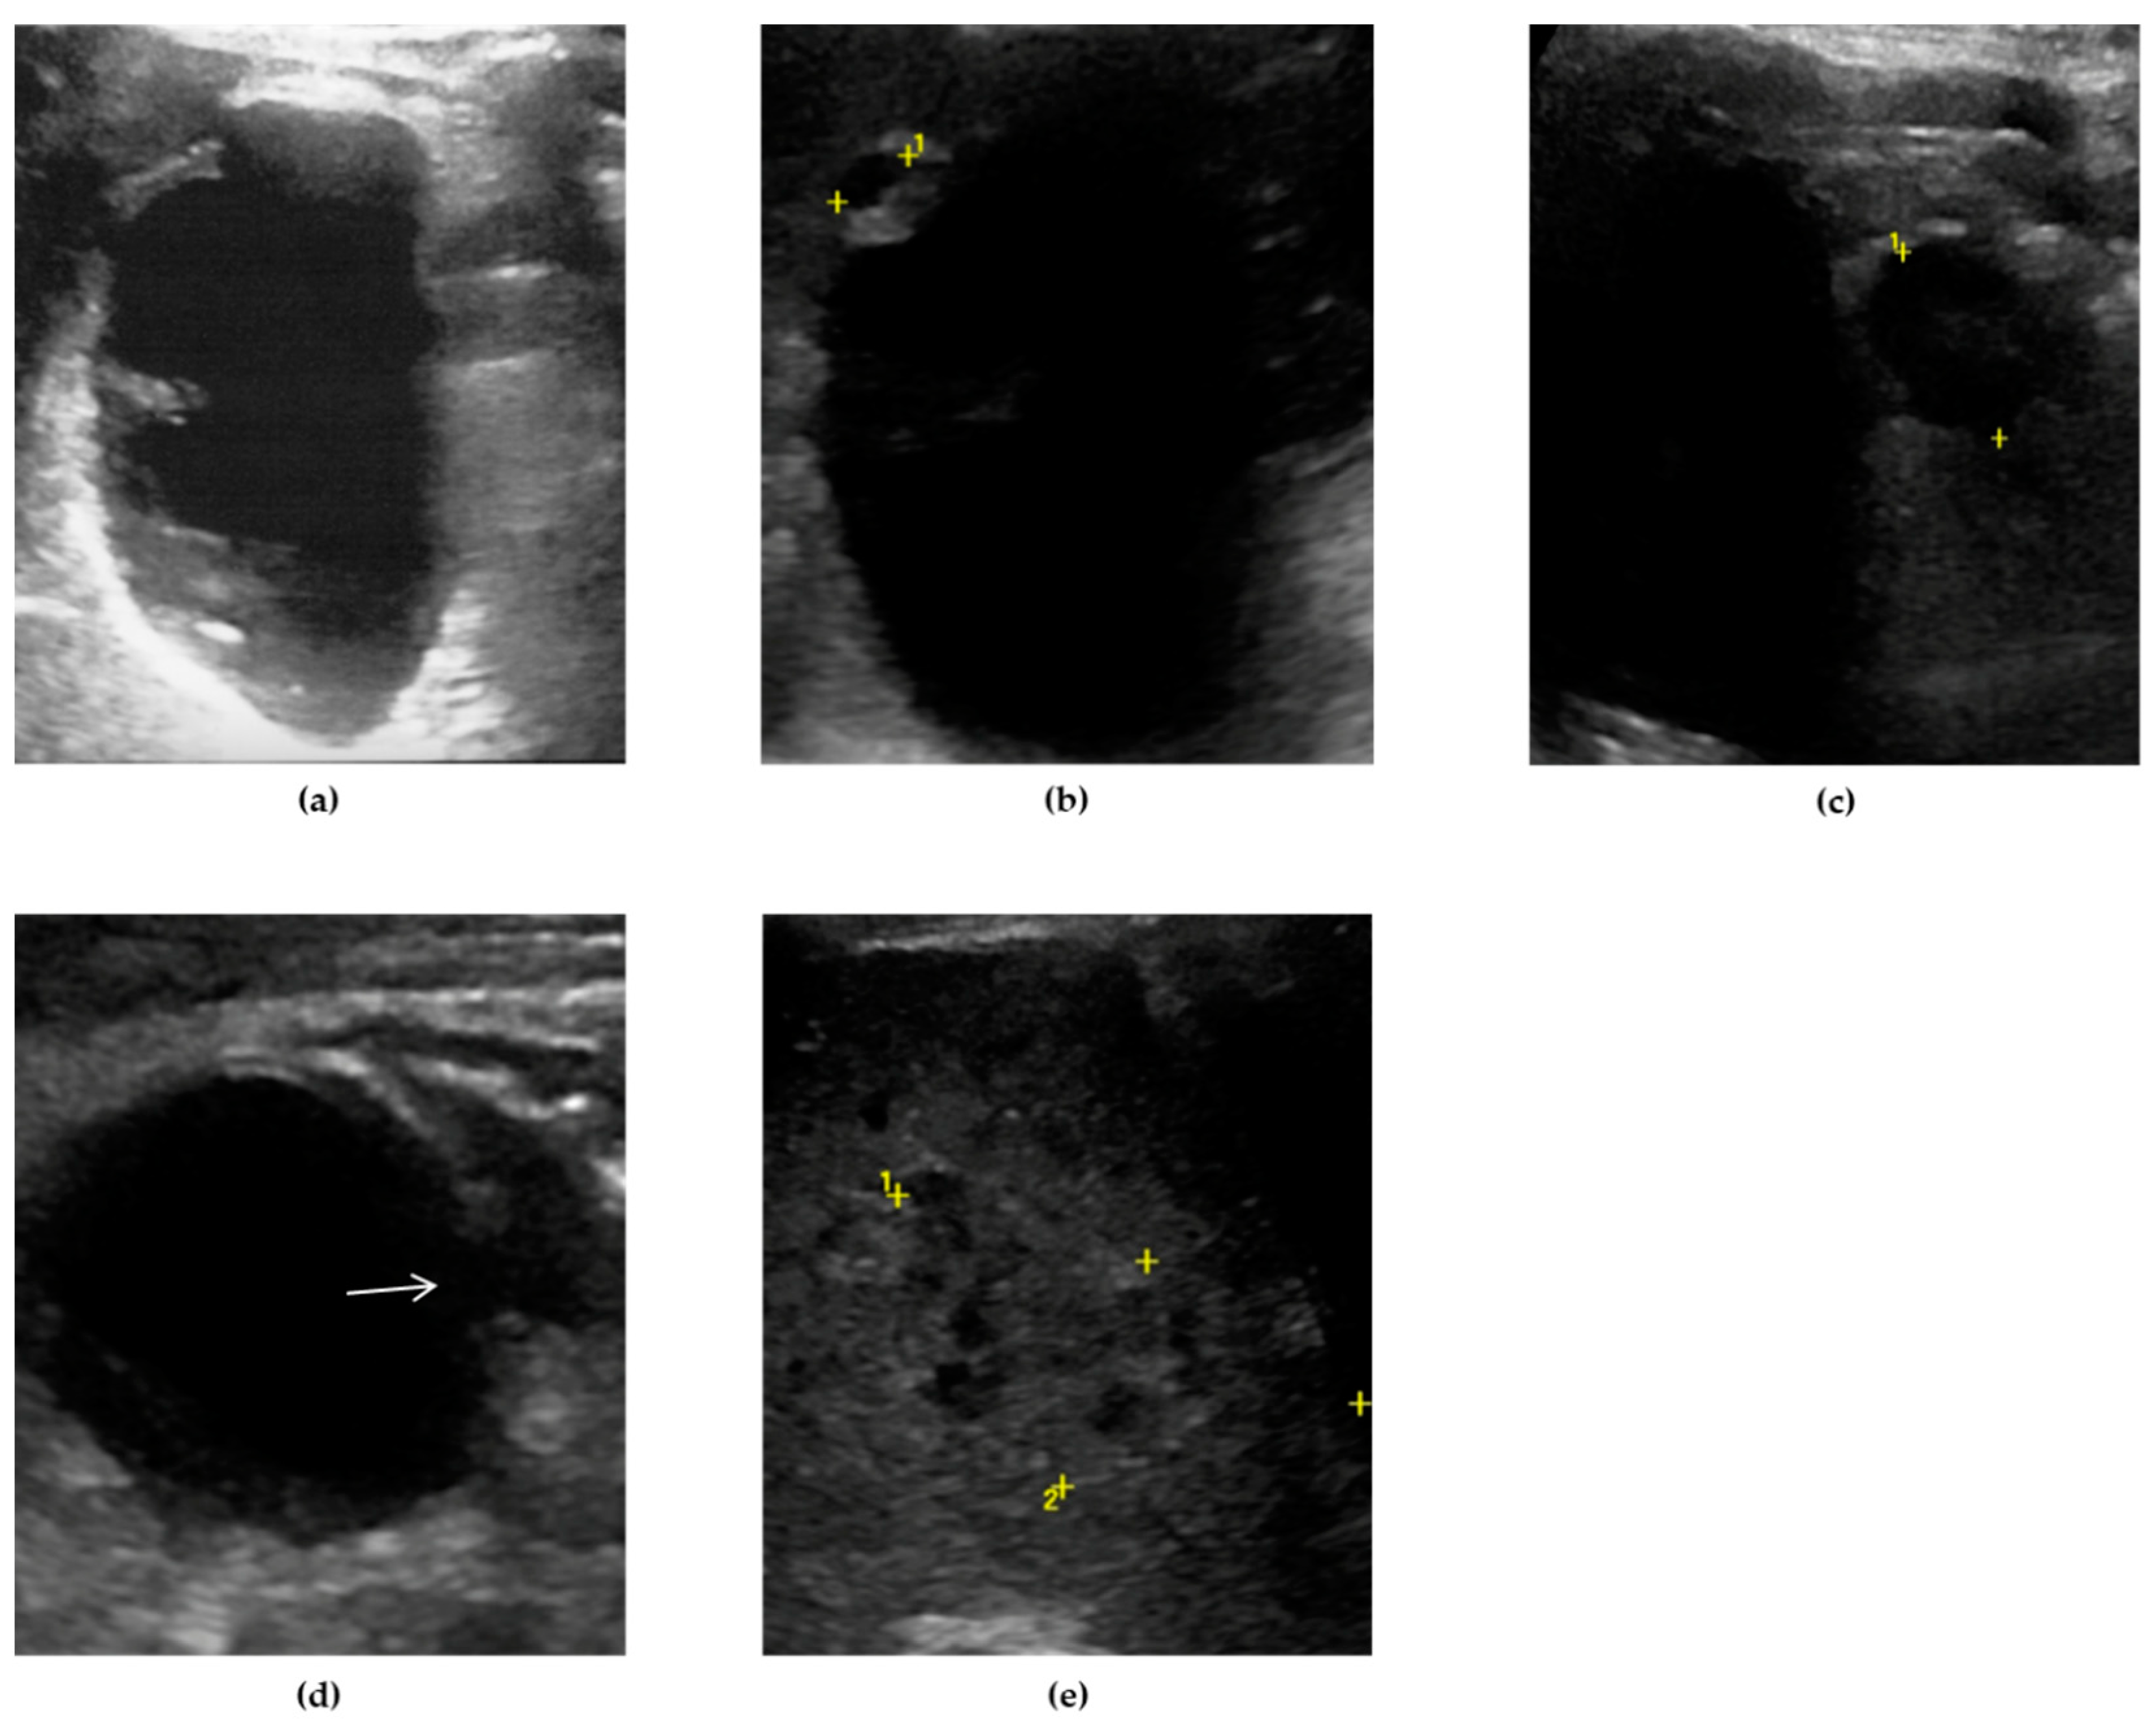

Sometimes, the adjacent liver parenchyma may show findings suggestive of diffuse edema, such as a hypoechoic aspect, possibly with prominent echogenic portal triads, known as “starry-sky” appearance (Figure 2). [29,32]

The most common sonographic finding in GC is an irregular gallbladder wall thickening,[49,50] characterized by multiple striations with alternating hypoechoic or hyperechoic bands (Figure 2). [27] This sonographic pattern is due to the presence of intramural hemorrhage or micro-abscesses. [3,44] Intraluminal membranes, formed by strands of fibrinous exudate and desquamated or “denuded” mucosa, are considered a more specific finding in GC, although less common (Figure 3).[3,44,49,50]

In presence of edema and necrosis, MVFI can show the alterations of the gallbladder wall already described by CEUS (Figure 2).

Typically, at US examination the gallbladder is distended and contains intraluminal echogenic material [76] without posterior acoustic shadows, lying in the dependent portion of the lumen. The echogenic material moves as the patient’s position change, usually resembling biliary sludge (Figure 2). [70] Additional sonographic findings of GE are gallbladder wall thickening and pericholecystic fluid. [76,77] Rarely, the presence of intraluminal air been reported, suggesting infection by anaerobic pathogens such as Clostridium or Bacteroides. [77]